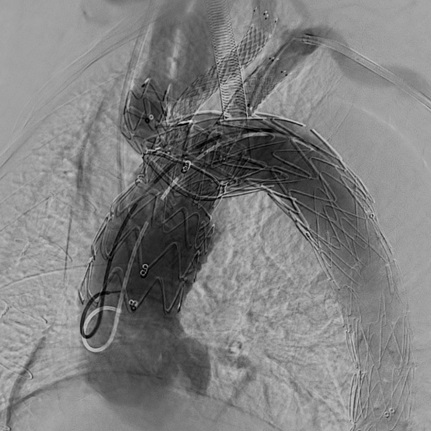

Przy użyciu lasera eksimerowego z przezskórnych dostępów naczyniowych (nakłucie igłą) przez lewą tętnicę szyjną wspólną oraz lewą tętnicę podobojczykową wykonano fenestrację poszycia implantowanego jednoczasowo stentgraftu, a następnie przez powstałe otwory, przy użyciu stentów krytych zaopatrzono powyższe naczynia, uzyskując przepływ przez wszystkie gałęzie łuku aorty.

Zabieg wykonano w całości przezskórnie, a implantacja systemu przebiegała z wykorzystaniem techniki szybkiej stymulacji komorowej (ang. rapid ventricular pacing).

Operacja odbyła się bez powikłań. Zarówno kontrolna arteriografia, jak i angio-TK po zabiegu wykazały wyłączenie z układu krążenia rozwarstwienia w obrębie łuku aorty oraz prawidłowy przepływ krwi w tętnicach domózgowych.